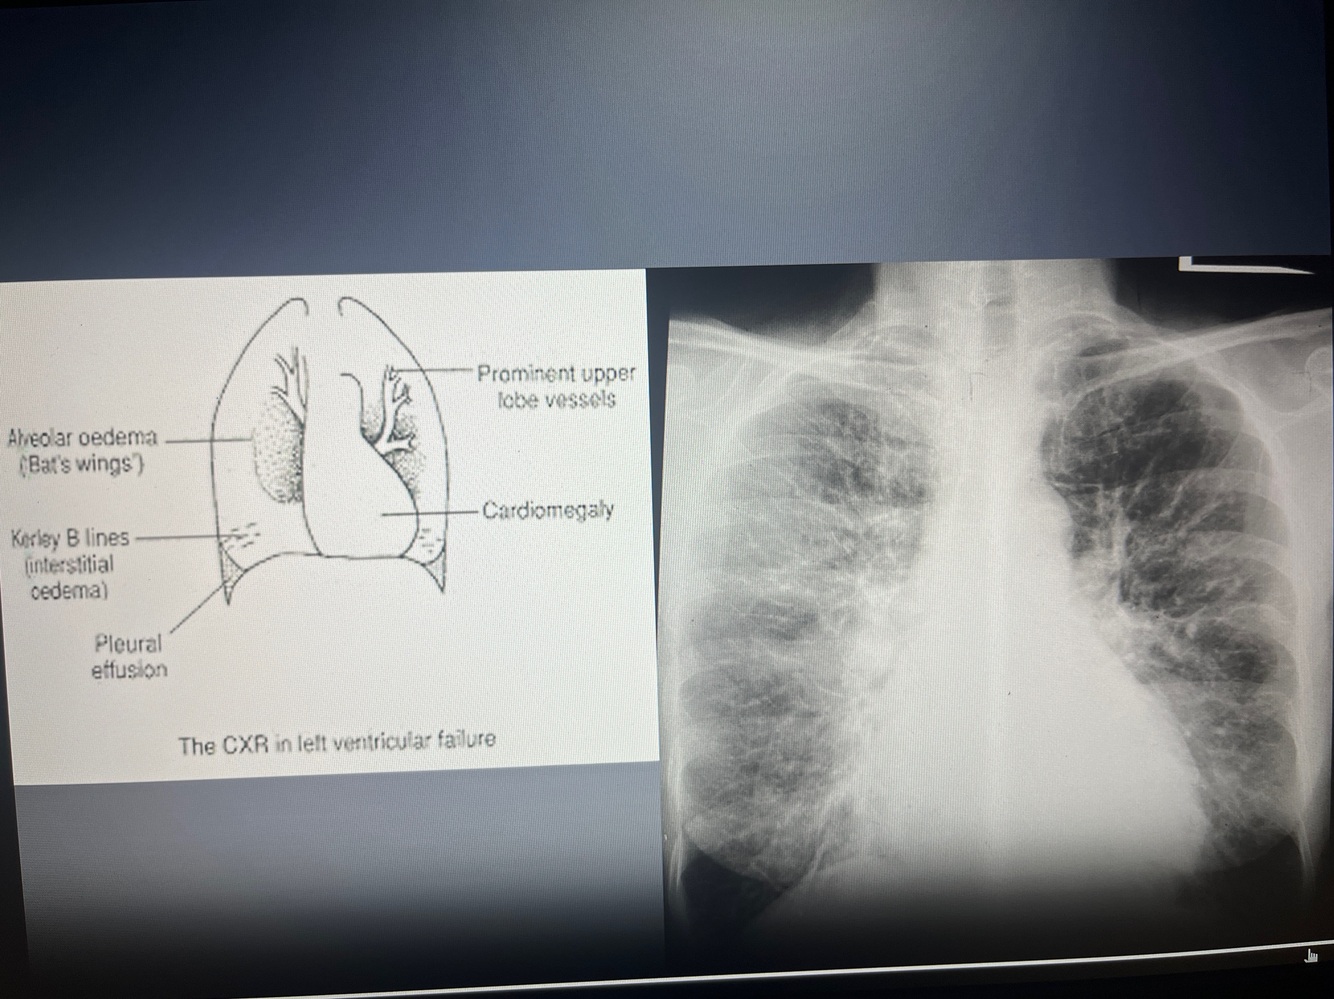

Q

Stages of congestive heart failure

A

Acute congestive heart failure